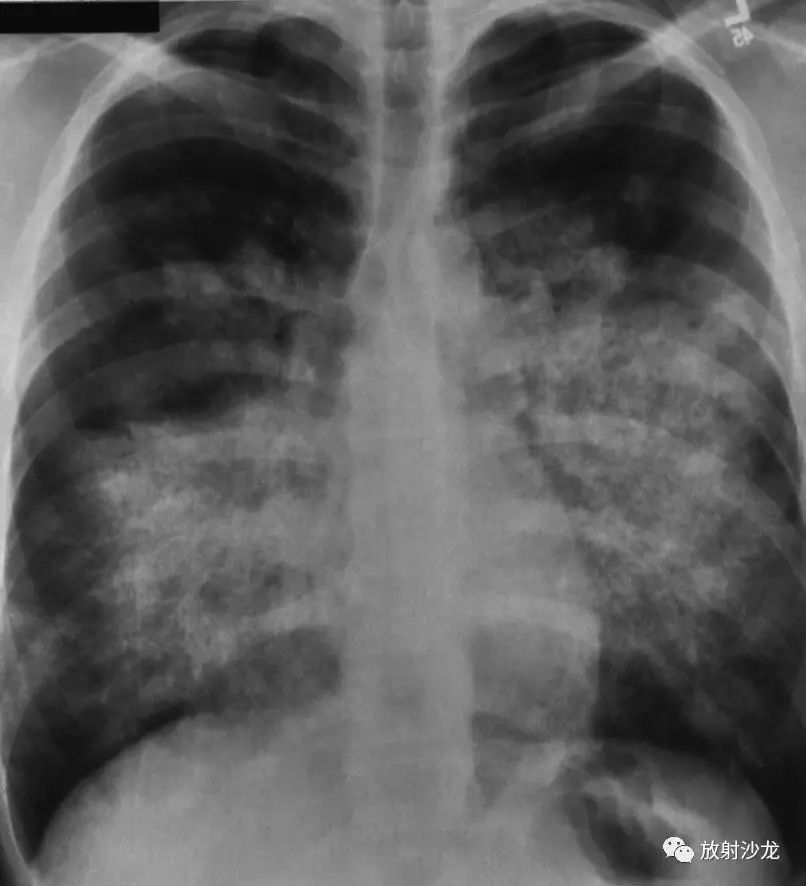

pcp影像学:以肺门为中心,蝴蝶状,不累及胸膜

5-1cm大小,边缘模糊,很快融合成斑片或大片状阴影,有含气支气管影像.

以双侧肺门为中心对称分布的大片状致密影,肺门区密度较高,边缘模糊

病灶为广泛的两侧对称性密度增高影,靠近肺门最明显,肺野周围部则逐渐

图 3 全胸片示心影增大,典型「蝴蝶影」,双侧肋膈角钝模糊,提示心衰

发热,ct如下:乍一看,很像心源性肺水肿,病灶沿着肺门分布,呈蝴蝶状